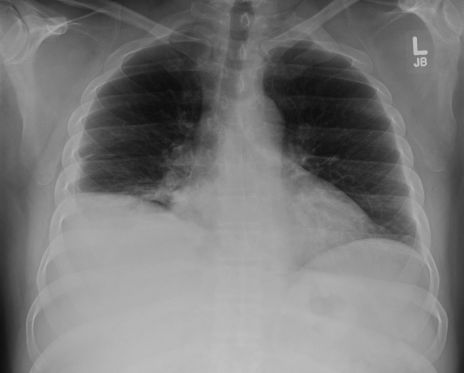

Yuri’s x-ray 24 hours later. The right lung is a white-out.

I discuss Yuri’s case with the specialist, and order IV antibiotics. We decide against inserting a larger tube as the fluid may be within the lung, not outside it. With supplemental oxygen, intravenous steroids, and inhalation treatments to open his airways, he settles overnight. The next day, a CT scan shows multiple pus pockets in and around the lung. Days later, when he’s stable, he’s taken to the operating room to clean out his lung and pleural space. He would spend almost a month in hospital, and continue on antibiotics for three weeks after that. Months later, the illness is just a bad memory, and he has no signs of recurrence.

Just curious – did the radiologist report the first radiograph as normal? The right hemi-diaphragm is elevated. The positioning isn’t ideal, there seems to be a bit or lordosis, so was the image taken sitting, perhaps? But i don’t buy that the first radiograph is normal — there is blunting of the right costophrenic angle. The heart occupies more than half of the chest transverse dimension. Trachea is deviated slightly to the right… Overall poor inspiratory effort.

I really hope, and expect, that the radiologist did NOT report that first image as normal.